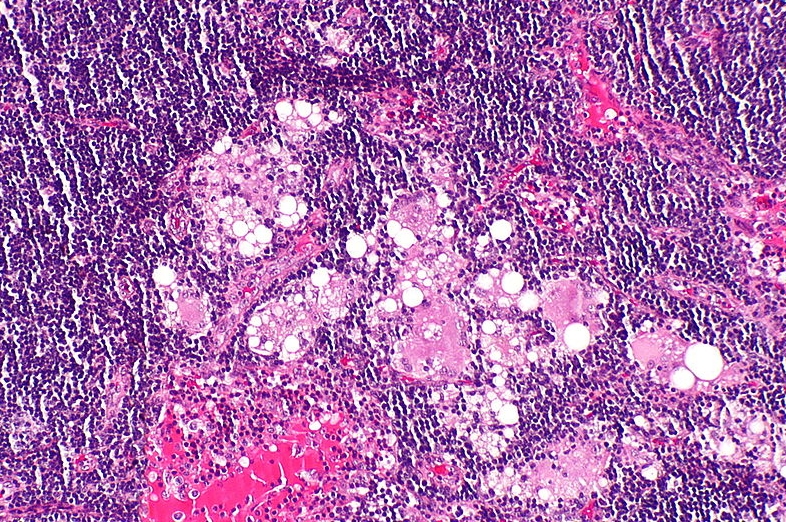

임파선 염은 단순히 임파선의 염증을 지칭하는 용어입니다. 하지만 임파선이란 무엇일까요? 임파선은 우리 몸의 작은 지킴이라고 생각하면 됩니다.

임파선은 우리 몸의 여러 부위에 배치되어 감염으로부터 몸을 보호하기 위해 열심히 일하는 경비원과 같은 역할을 합니다. 하지만 때때로 임파선에 염증이 생길 수 있는데, 바로 이때 임파선 염에 대해 이야기합니다.

임파선 염을 유발하는 감염의 경우 일반적으로 박테리아가 원인입니다. 이 교활한 작은 유기체는 다양한 경로를 통해 우리 몸에 침투할 수 있습니다.

일단 임파선에 침입하면 임파선이 이를 감지하고 반격을 시작합니다. 이러한 방어 메커니즘이 염증을 유발합니다.